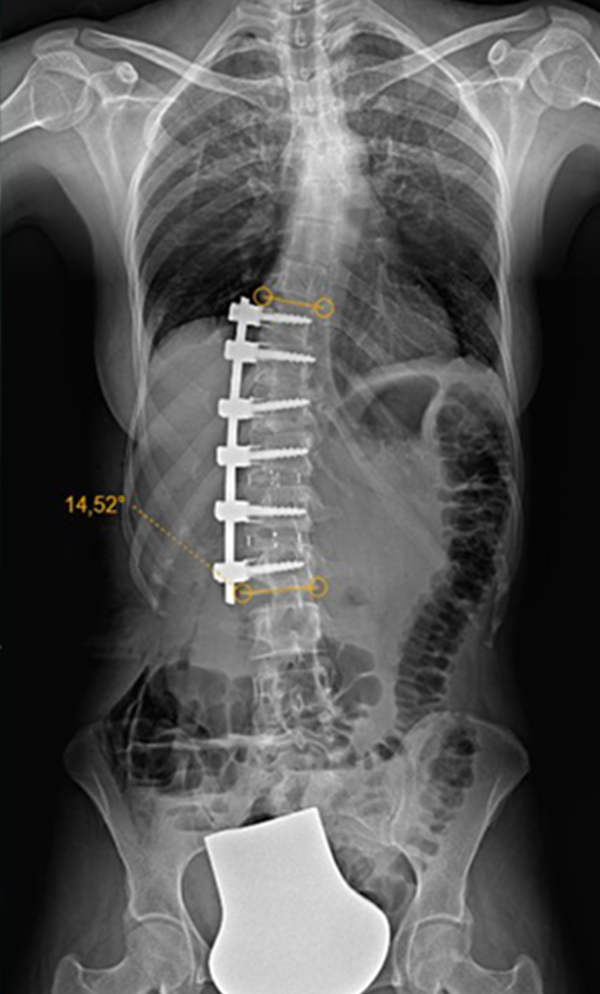

Gallery : Before - After